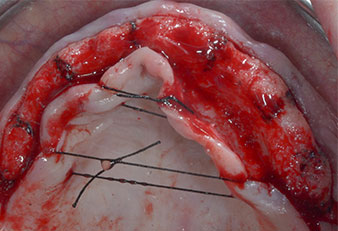

Tres años después, llegó el momento de colocar una prótesis del mismo tipo en el maxilar superior. Basándose en una planificación mediante tomografía computarizada de haz cónico (CBCT, por sus siglas en inglés), se evitó la necesidad de realizar una elevación del seno utilizando implantes cortos, mientras que una plantilla quirúrgica sirvió para transferir las posiciones planificadas al borde alveolar (figuras 1 y 2).

Para marcar las posiciones del implante y realizar la preparación piloto, se utilizó un inserto piezoeléctrico (Piezomed I1) con revestimiento de diamante y forma de llama (figura 3). Se tomaron precauciones para realizar movimientos hacia arriba y hacia abajo, con una potencia reducida, una irrigación completa y una baja presión (por debajo de 300 g). A continuación, se aplicó un inserto piloto (Piezomed I2A/I2P) para aumentar el diámetro inicial de 2 mm de los sitios de implante (figura 4), seguido de un inserto de 3 mm (Fig. 5).

Debido al hueso relativamente duro (D2) existente en el sector anterior, los sitios de los implantes largos de 10 mm de las posiciones 11 y 21 se finalizaron con una fresa rotatoria de 4 mm de diámetro, en combinación con un contra-ángulo quirúrgico WS-75 L de W&H, el motor de implantes Implantmed de W&H y el módulo opcional Osstell ISQ de W&H. En cambio, debido a la existencia de hueso blando, los sitios posteriores se prepararon hasta un diámetro final de 3 mm utilizando el inserto Piezomed I3P. Por último, los implantes se colocaron a nivel crestal para su osteointegración durante tres meses (figuras 6-10). La prótesis existente se mantuvo sobre cuatro implantes provisionales (figura 8).